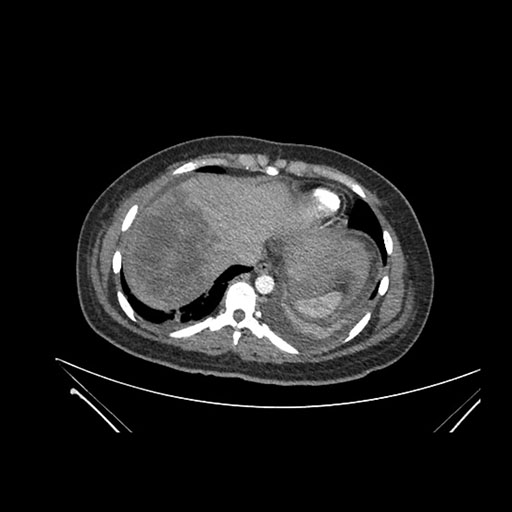

Imaging Analysis

Look through the patient's CT scan to identify any areas of concern for the necessary procedure.

Axial Arterial

Based on initial findings, which issue(s) would you be most concerned about?